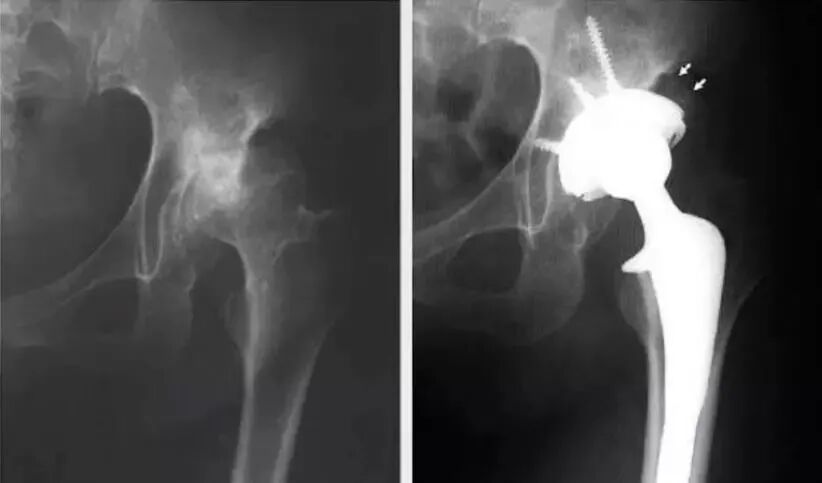

①术前模板测量,假体安放设计:(可借助模板或CT测量)

②髋臼侧:需要多大的臼,是涂层还是金属骨小梁,是否需要加强杯;准备把髋臼放在什么位置?(旋转中心)多大角度?(前倾,外展),有没有足够的骨量(是否需植骨);

髋臼模板测量:

①选择骨盆正位片与合适比例模板;

②将模板按照45°倾斜角度放入髋臼;

③估计锉后髋臼的大小,内壁的厚度;

④假体的大小应与软骨下最少的截骨量一致;

⑤假体的中心与原髋臼的旋转中心尽可能一致。